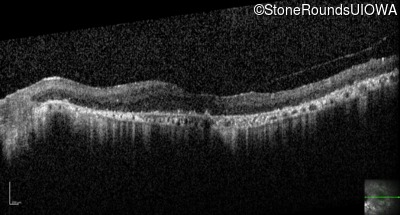

Optical Coherence Tomography - Right - 3/120

Exemplar / OCT Stack

OCT Stack